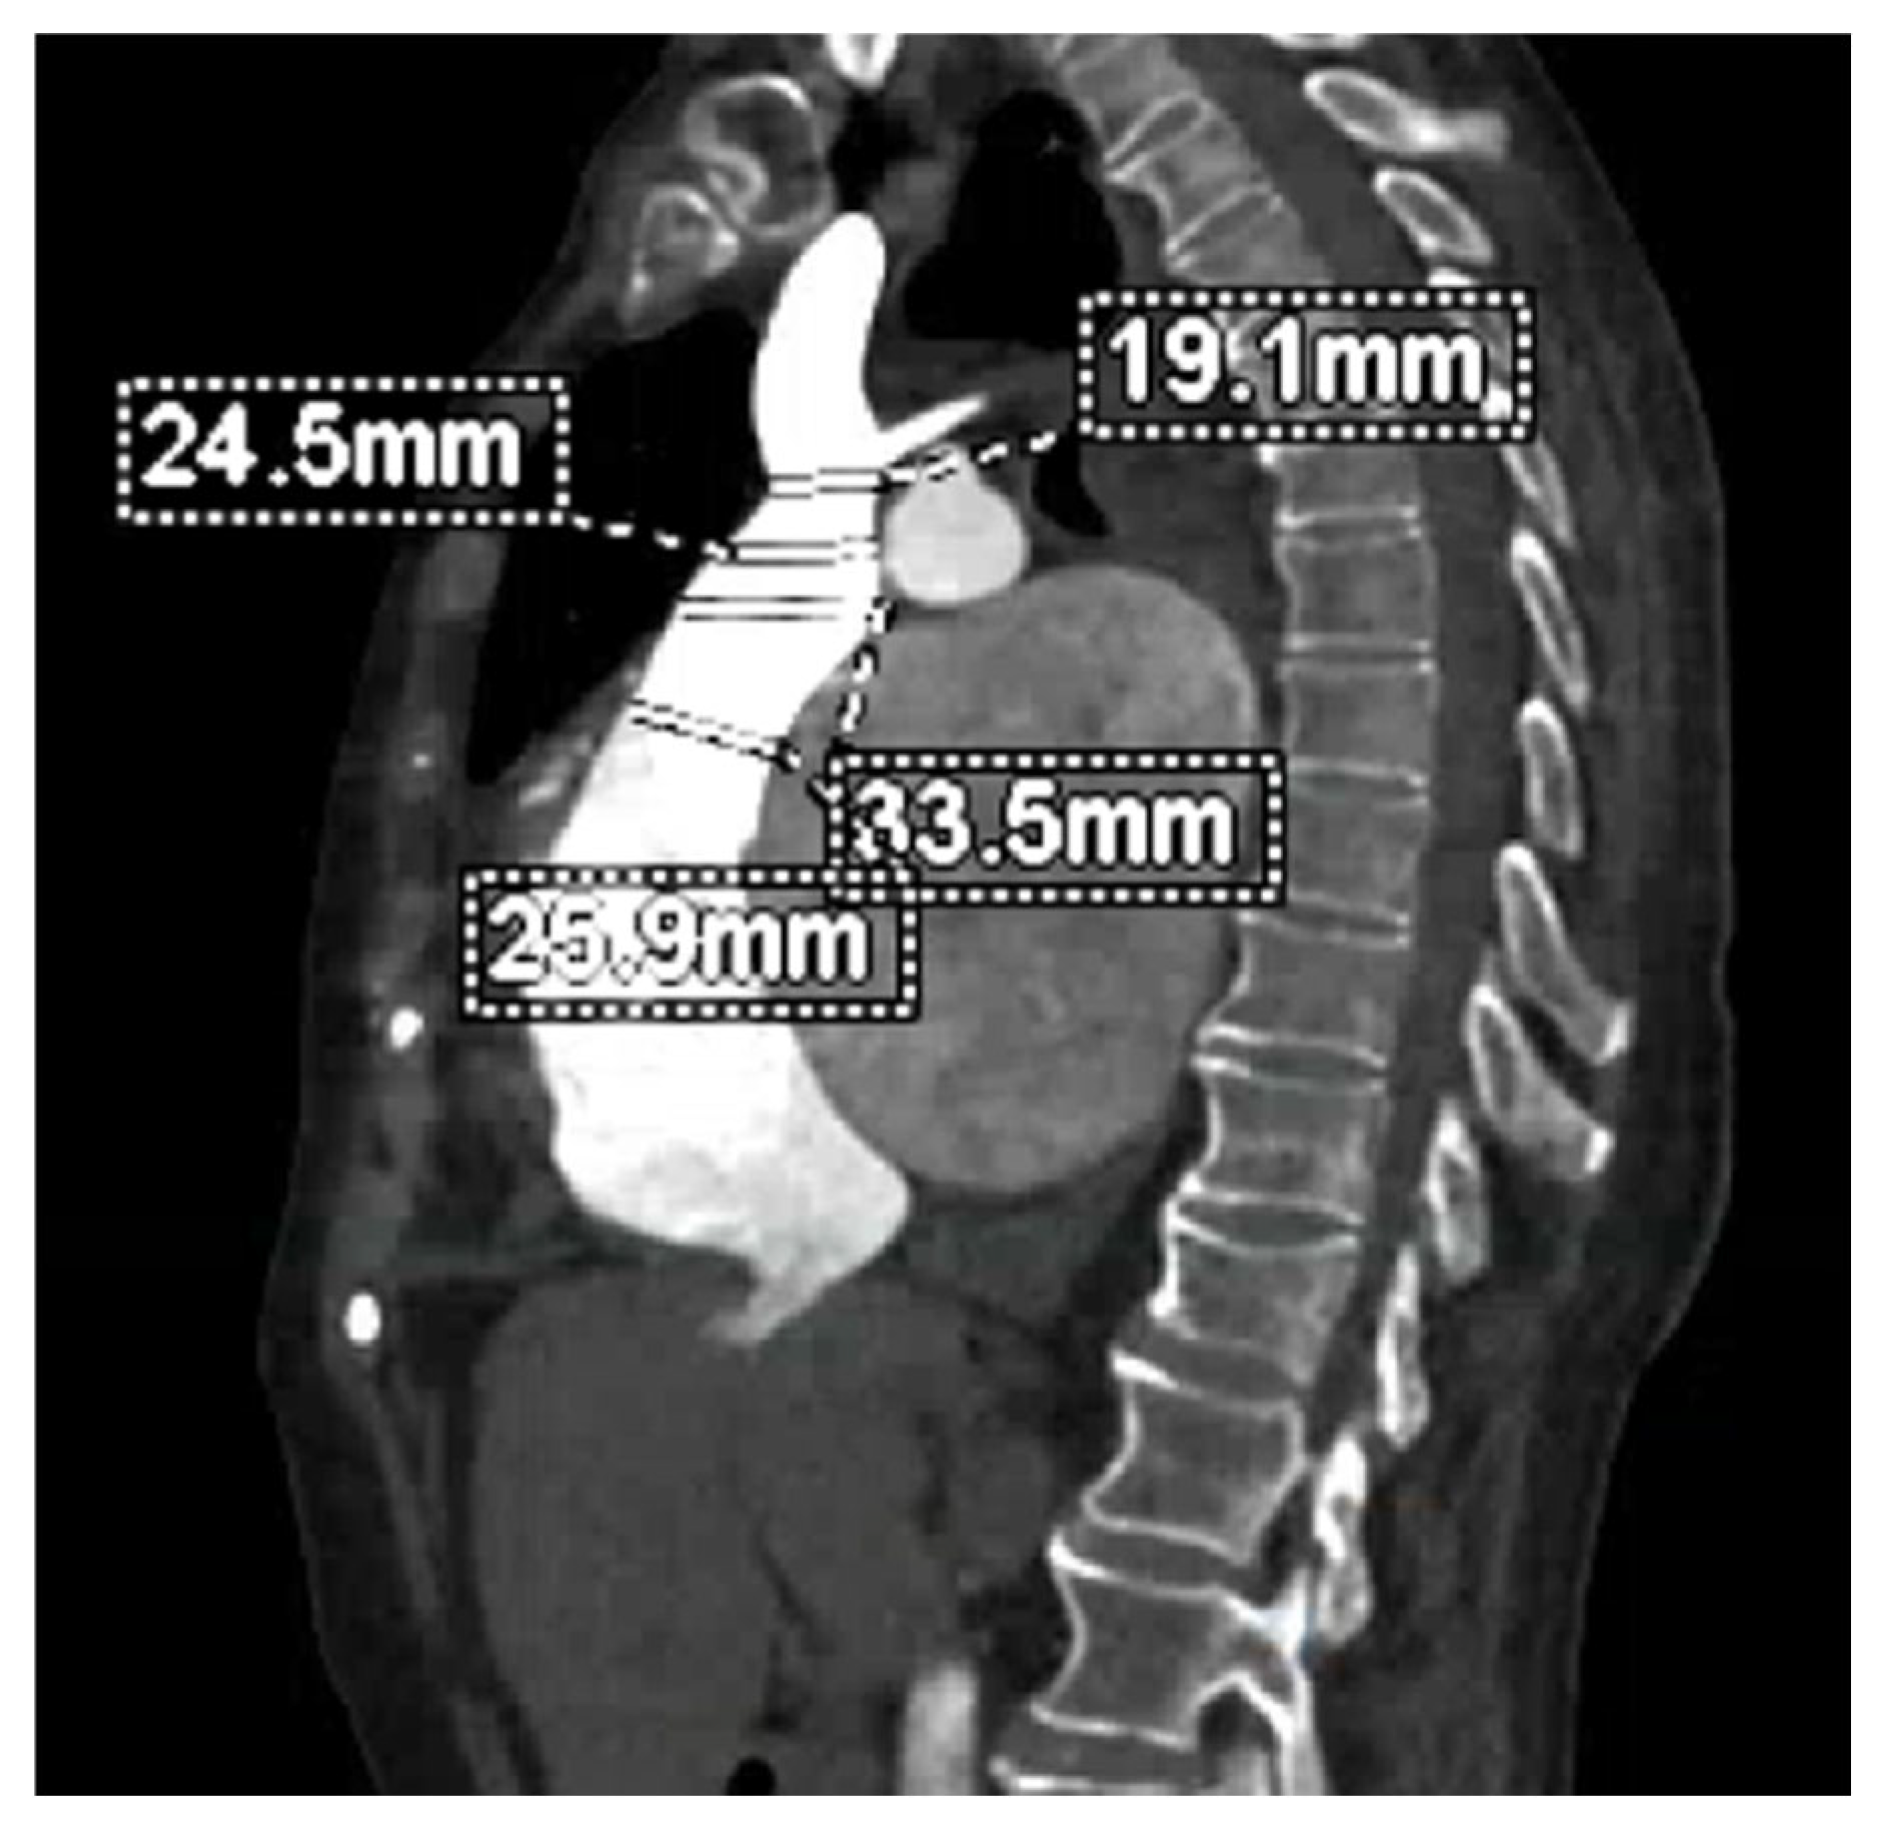

- Hell, M.M.; Emrich, T.; Kreidel, F.; Kreitner, K.-F.; Schoepf, U.J.; Münzel, T.; Von Bardeleben, R.S. Computed Tomography Imaging Needs for Novel Transcatheter Tricuspid Valve Repair and Replacement Therapies. Eur. Heart J. Cardiovasc. Imaging 2021, 22, 601–610. [Google Scholar] [CrossRef]

- Cammalleri, V.; Carpenito, M.; De Stefano, D.; Ussia, G.P.; Bono, M.C.; Mega, S.; Nusca, A.; Cocco, N.; Nobile, E.; De Filippis, A.; et al. Novel Computed Tomography Variables for Assessing Tricuspid Valve Morphology: Results from the TRIMA (Tricuspid Regurgitation IMAging) Study. J. Clin. Med. 2022, 11, 2825. [Google Scholar] [CrossRef]

- Van Rosendael, P.J.; Kamperidis, V.; Kong, W.K.F.; Van Rosendael, A.R.; Van Der Kley, F.; Ajmone Marsan, N.; Delgado, V.; Bax, J.J. Computed Tomography for Planning Transcatheter Tricuspid Valve Therapy. Eur. Heart J. 2017, 38, 665–674. [Google Scholar] [CrossRef] [PubMed]

- Hinzpeter, R.; Eberhard, M.; Burghard, P.; Tanner, F.; Taramasso, M.; Manka, R.; Feuchtner, G.; Maisano, F.; Alkadhi, H. Computed Tomography in Patients with Tricuspid Regurgitation Prior to Transcatheter Valve Repair: Dynamic Analysis of the Annulus with an Individually Tailored Contrast Media Protocol. EuroIntervention 2017, 12, e1828–e1836. [Google Scholar] [CrossRef] [PubMed]